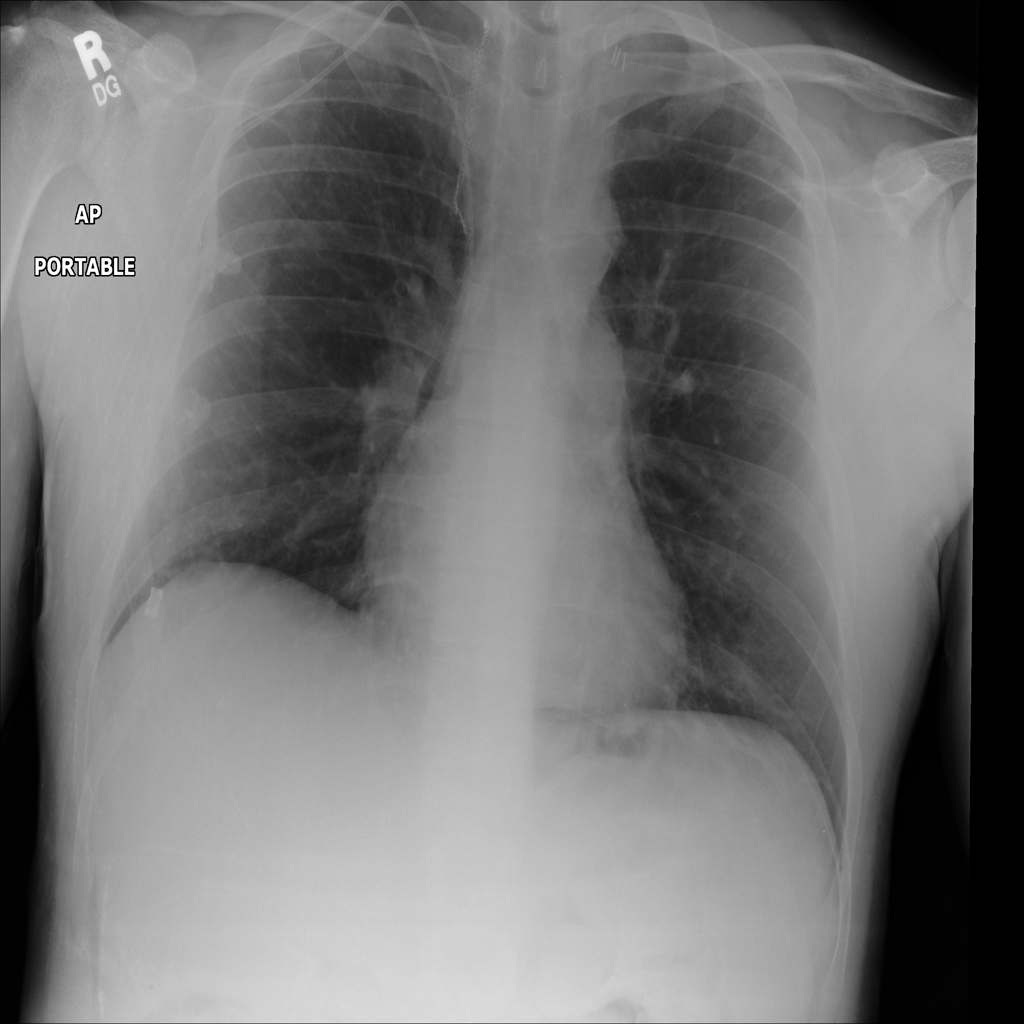

PAT-4639 · IMG-013Pneumothorax

PAT-4639 · IMG-013

AP